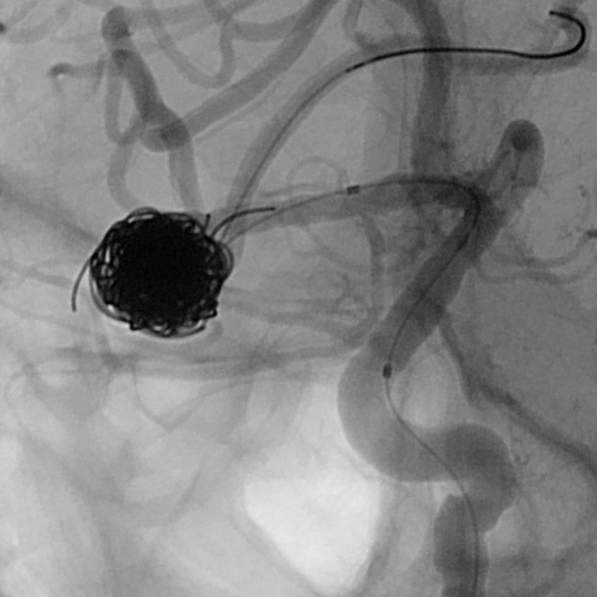

最终,动脉瘤瘤体致密栓塞,各个分支保留良好

粗大分支从破裂瘤体上发出来,急性期能单纯致密栓塞吗?